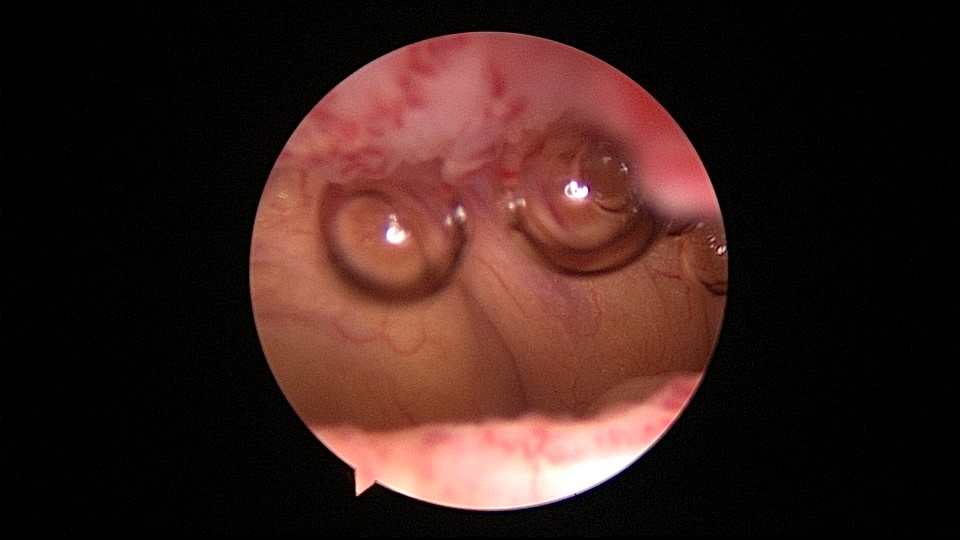

很有意思的一次取环经历:患者33岁,G2P1,剖宫产1次。安环7年,月经淋漓不尽3个月,2家医院取环失败,两次取环时间相隔24天,第二次取环失败后第二天到我院行宫腔镜取环。子宫后倾后屈位,剖宫产切口憩室处组织杂乱,爱母环位置正常,感觉是个比较简单的取环,取环钩探寻节育环,顺利取出。用刮匙准备诊刮,刮匙很容易进入,感觉很深,达13cm,但前面宫腔镜检查没有异常,以为是B超测量子宫有误,或者剖宫产粘连把子宫拉上去了,没有往子宫穿孔方面想,刮匙试探几次均是相同结果,试着刮了几下,没有内膜组织,再次置镜检查,结果镜子进入盆腔,看见网膜脂肪组织。宫颈内口闭塞,花了较多时间也进不去宫腔,穿孔处无出血,盆腔无积血,放弃诊刮。打电话给第二家取环医院的医生,得知前一天取环时感觉穿孔,放弃取环,介绍到我这里宫腔镜取环。分析整个过程,第一家医院在切口憩室处已穿孔,取环失败,穿孔处虽然愈合,却是一个薄弱环节,第二家医院和我们的宫腔镜均在该处进入盆腔,刮匙探查有底,是因为刮匙抵到了骶骨。